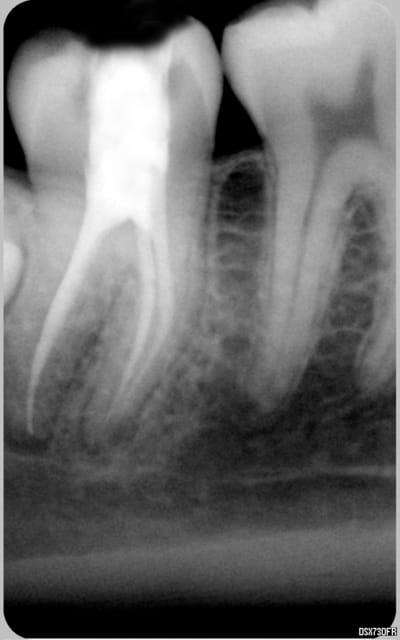

voila quelques traitements,modestes mais je suis encore jeune....

encore des radios,peut-etre assez moyen comme traitement...mais je vu pire...

Cher confrère roumain , tu as sans doute remarqué que lorsque tu réalises de superbes endos sur molaires ( félicitations au vue des radios) tu es rémunéré généreusement par ton patient un peu plus de 80 euros le traitement complet .

Comme tu as pu le constater dans ton beau pays, les soins conservateurs qui représentent 70% de notre activité journalière sont au bas mot remboursé le double , triple voir le quadruple en l'occurrence pour une bio sur molaire ( 100 euros le canal sur certains sites qui font leur pub sur Eugénol ).